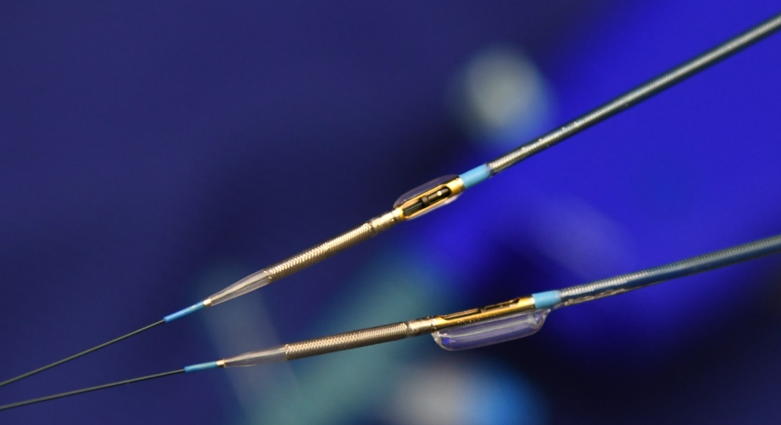

ダイアモンドバック

ロータブレーターと同じくダイヤモンドチップのドリルですが、重心がカテーテルの中心より外側に偏位しており、高速回転の遠心力で側面の石灰化を削り取ります。ロータブレーターとは病変により使い分けます。

DCA(方向性冠動脈粥腫切除術)

冠動脈のプラークを切除し、体外に取り出します。プラーク量が減ることで狭窄が解除され、場合によってはステントを留置せずに治療を終えることもできます。